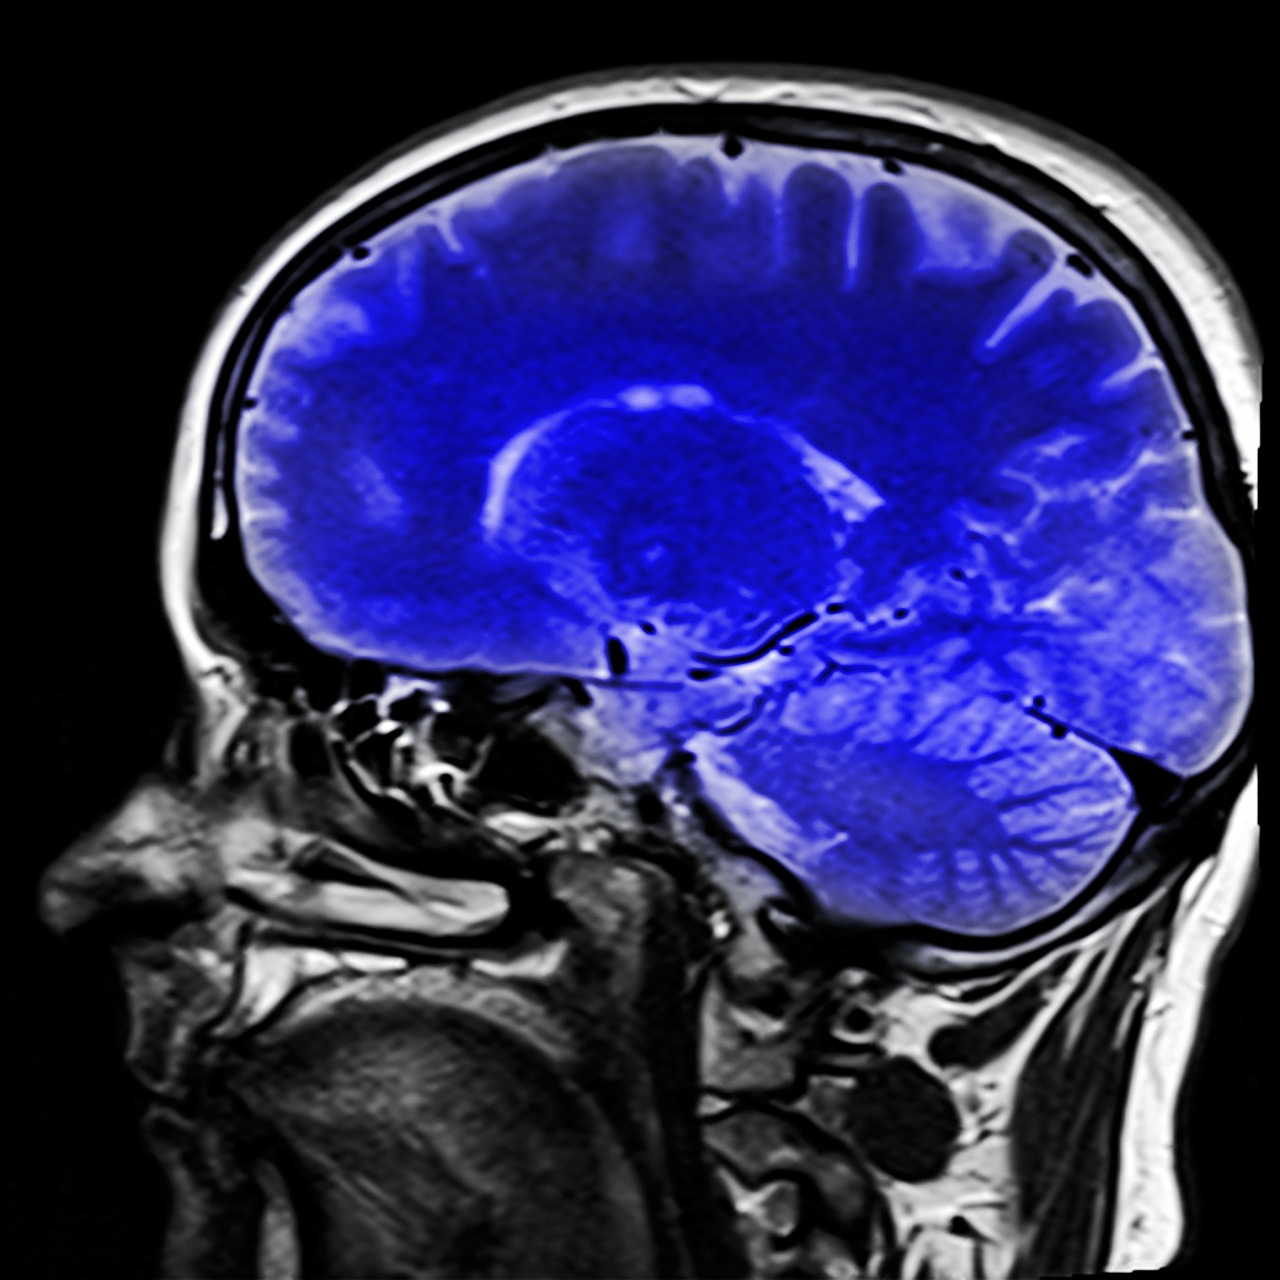

Conocer la composición milimétrica de un tejido humano, estudiar el intercambio de sustancias en el organismo a nivel molecular y lograr representaciones de diagnóstico médico con mayor resolución y alcance de lo actual, es posible gracias a una nueva generación de imágenes por resonancia magnética desarrollada en la Facultad de Ciencias (FC) de la UNAM.

En vez de los 1.5 a 3 tesla (unidad de inducción magnética o densidad de flujo magnético) que utilizan los equipos convencionales, el nuevo –que está en experimentación– utilizará 15.2 tesla, explicó Jaime Fabián Vázquez de la Rosa, profesor de Física Médica en el Departamento de Física de la FC.

Esto trae consigo ventajas: evitar causar incomodidad a los pacientes y que en los llamados ultra altos campos magnéticos se produzca una excitación de energía homogénea; es decir, que no haya pérdida de señal de la imagen. Con esta técnica, llamada de imagenología por onda viajera, se genera una imagen más homogénea, con lo que se logra mayor eficiencia.

Vázquez de la Rosa señaló que la resonancia magnética es tan versátil que permite lograr imágenes anatómicas y funcionales. Se pueden ver todo lo referente a tejidos blandos: hemorragias, coágulos, tumores y cartílagos, además de cómo consume oxígeno o energía el cerebro.